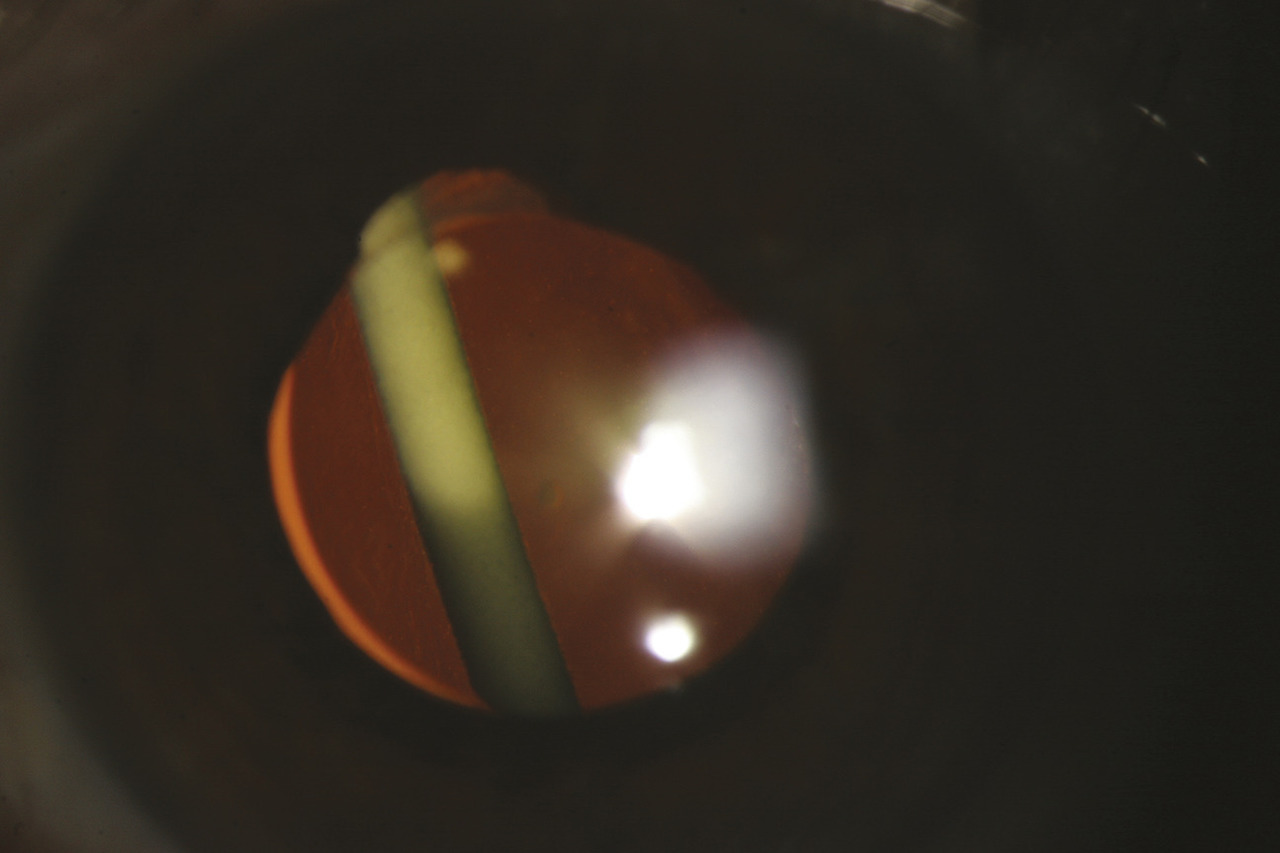

La voie d’injection intravitréenne de médicaments a été pour la première fois utilisée de manière généralisée pour le traitement des rétinites à cytomégalovirus, lorsque les thérapeutiques antirétrovirales n’étaient pas encore disponibles pour les patients atteints de sida. Cette voie d’injection s’est ensuite développée pour l’injection d’anti- vascular endothelial growth factor pour le traitement des formes néovascularisées de dégénérescence maculaire liée à l’âge. La thérapeutique des uvéites s’est également enrichie de ce mode d’administration avec la possibilité d’injecter une forme à libération prolongée de dexaméthasone. Ozurdex est un implant à biodégra- dation spontanée, destiné à une administration par injection intravitréenne et contenant 700 µg de dexaméthasone (fig. 3).3 Le béné- fice de l’injection d’Ozurdex sur l’inflammation du segment postérieur, en particulier sur l’œdème maculaire, peut être attendu pour une durée d’environ 3 mois et parfois plus. Les principales compli- cations de l’injection sont une hypertonie oculaire cortico-induite et l’apparition secondaire d’opacités cristalliniennes. D’autres produits injectables par voie intra- vitréenne, dont le tacrolimus, sont en cours d’évaluation pour le traitement des uvéites non infectieuses non antérieures.